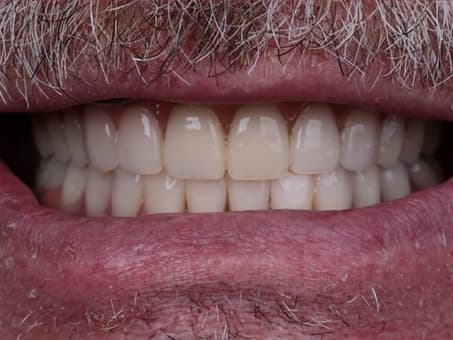

В стоматологической клинике Eurodent используются современные методы имплантации зубов, позволяющие достичь самых лучших результатов. Сюда входит широкий комплекс процедур, начиная от компьютерного сканирования зубных единиц до создания слепков и протезов на оборудовании с числовым програмным управлением. Использование программ позволяет исключить человеческий фактор и максимально автоматизировать процесс лечения.

В рамках навигационной имплантации все шаги проектируются и планируются в 3D-программе. Каждое движение хирурга осуществляется по направляющему шаблону. Кроме этого программа позволяет создать проект зубного протеза, который устанавливается сразу после оперативного вмешательства. Процедура проводится малотравматичным способом и позволяет учесть все физиологические особенности пациентов.

Зубные протезы изготавливают с помощью методики CAD/CAM — заготовка моделируется с помощью компьютерной программы и фрезеруется на ЧПУ станках. Эта методика применяется для работы с коронками, хирургическими шаблонами, абатментами, накладками, мостовидными конструкциями и позволяет достичь высокой точности при изготовлении протезов.

Протезы, изготовленные по старой технологии, изготавливались на основании слепка, были неудобными и массивными. Компьютерная имплантация зубов позволяет делать протезы без слепка на основании результатов сканирования, что гарантирует высокую точность и получение тонкой анатомически правильной модели.